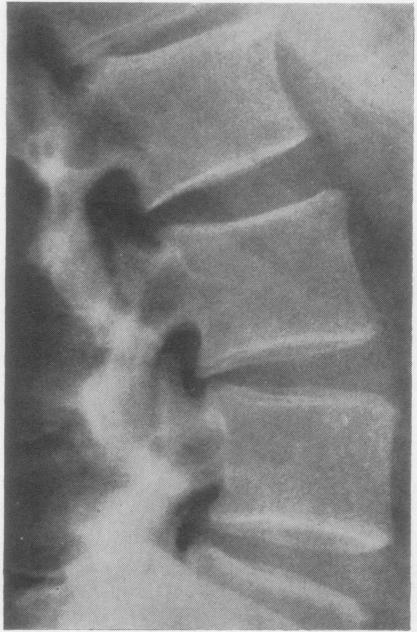

RHEUMATOID ARTHRITIS OF THE LUMBAR SPINE.

Ann Rheum Dis. 1964 May;23(3):205-17. doi: 10.1136/ard.23.3.205.